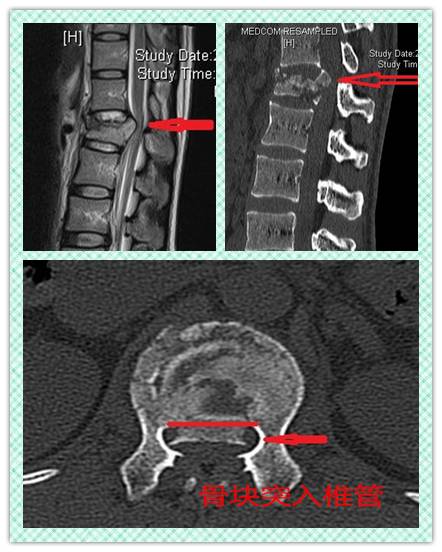

腰1椎体爆裂性骨折,整个椎体被暴力挤压后崩开往四周碎裂,骨折块向椎管内突入,压迫腰椎神经,可能引起下肢疼痛、麻木、无力甚至瘫痪。